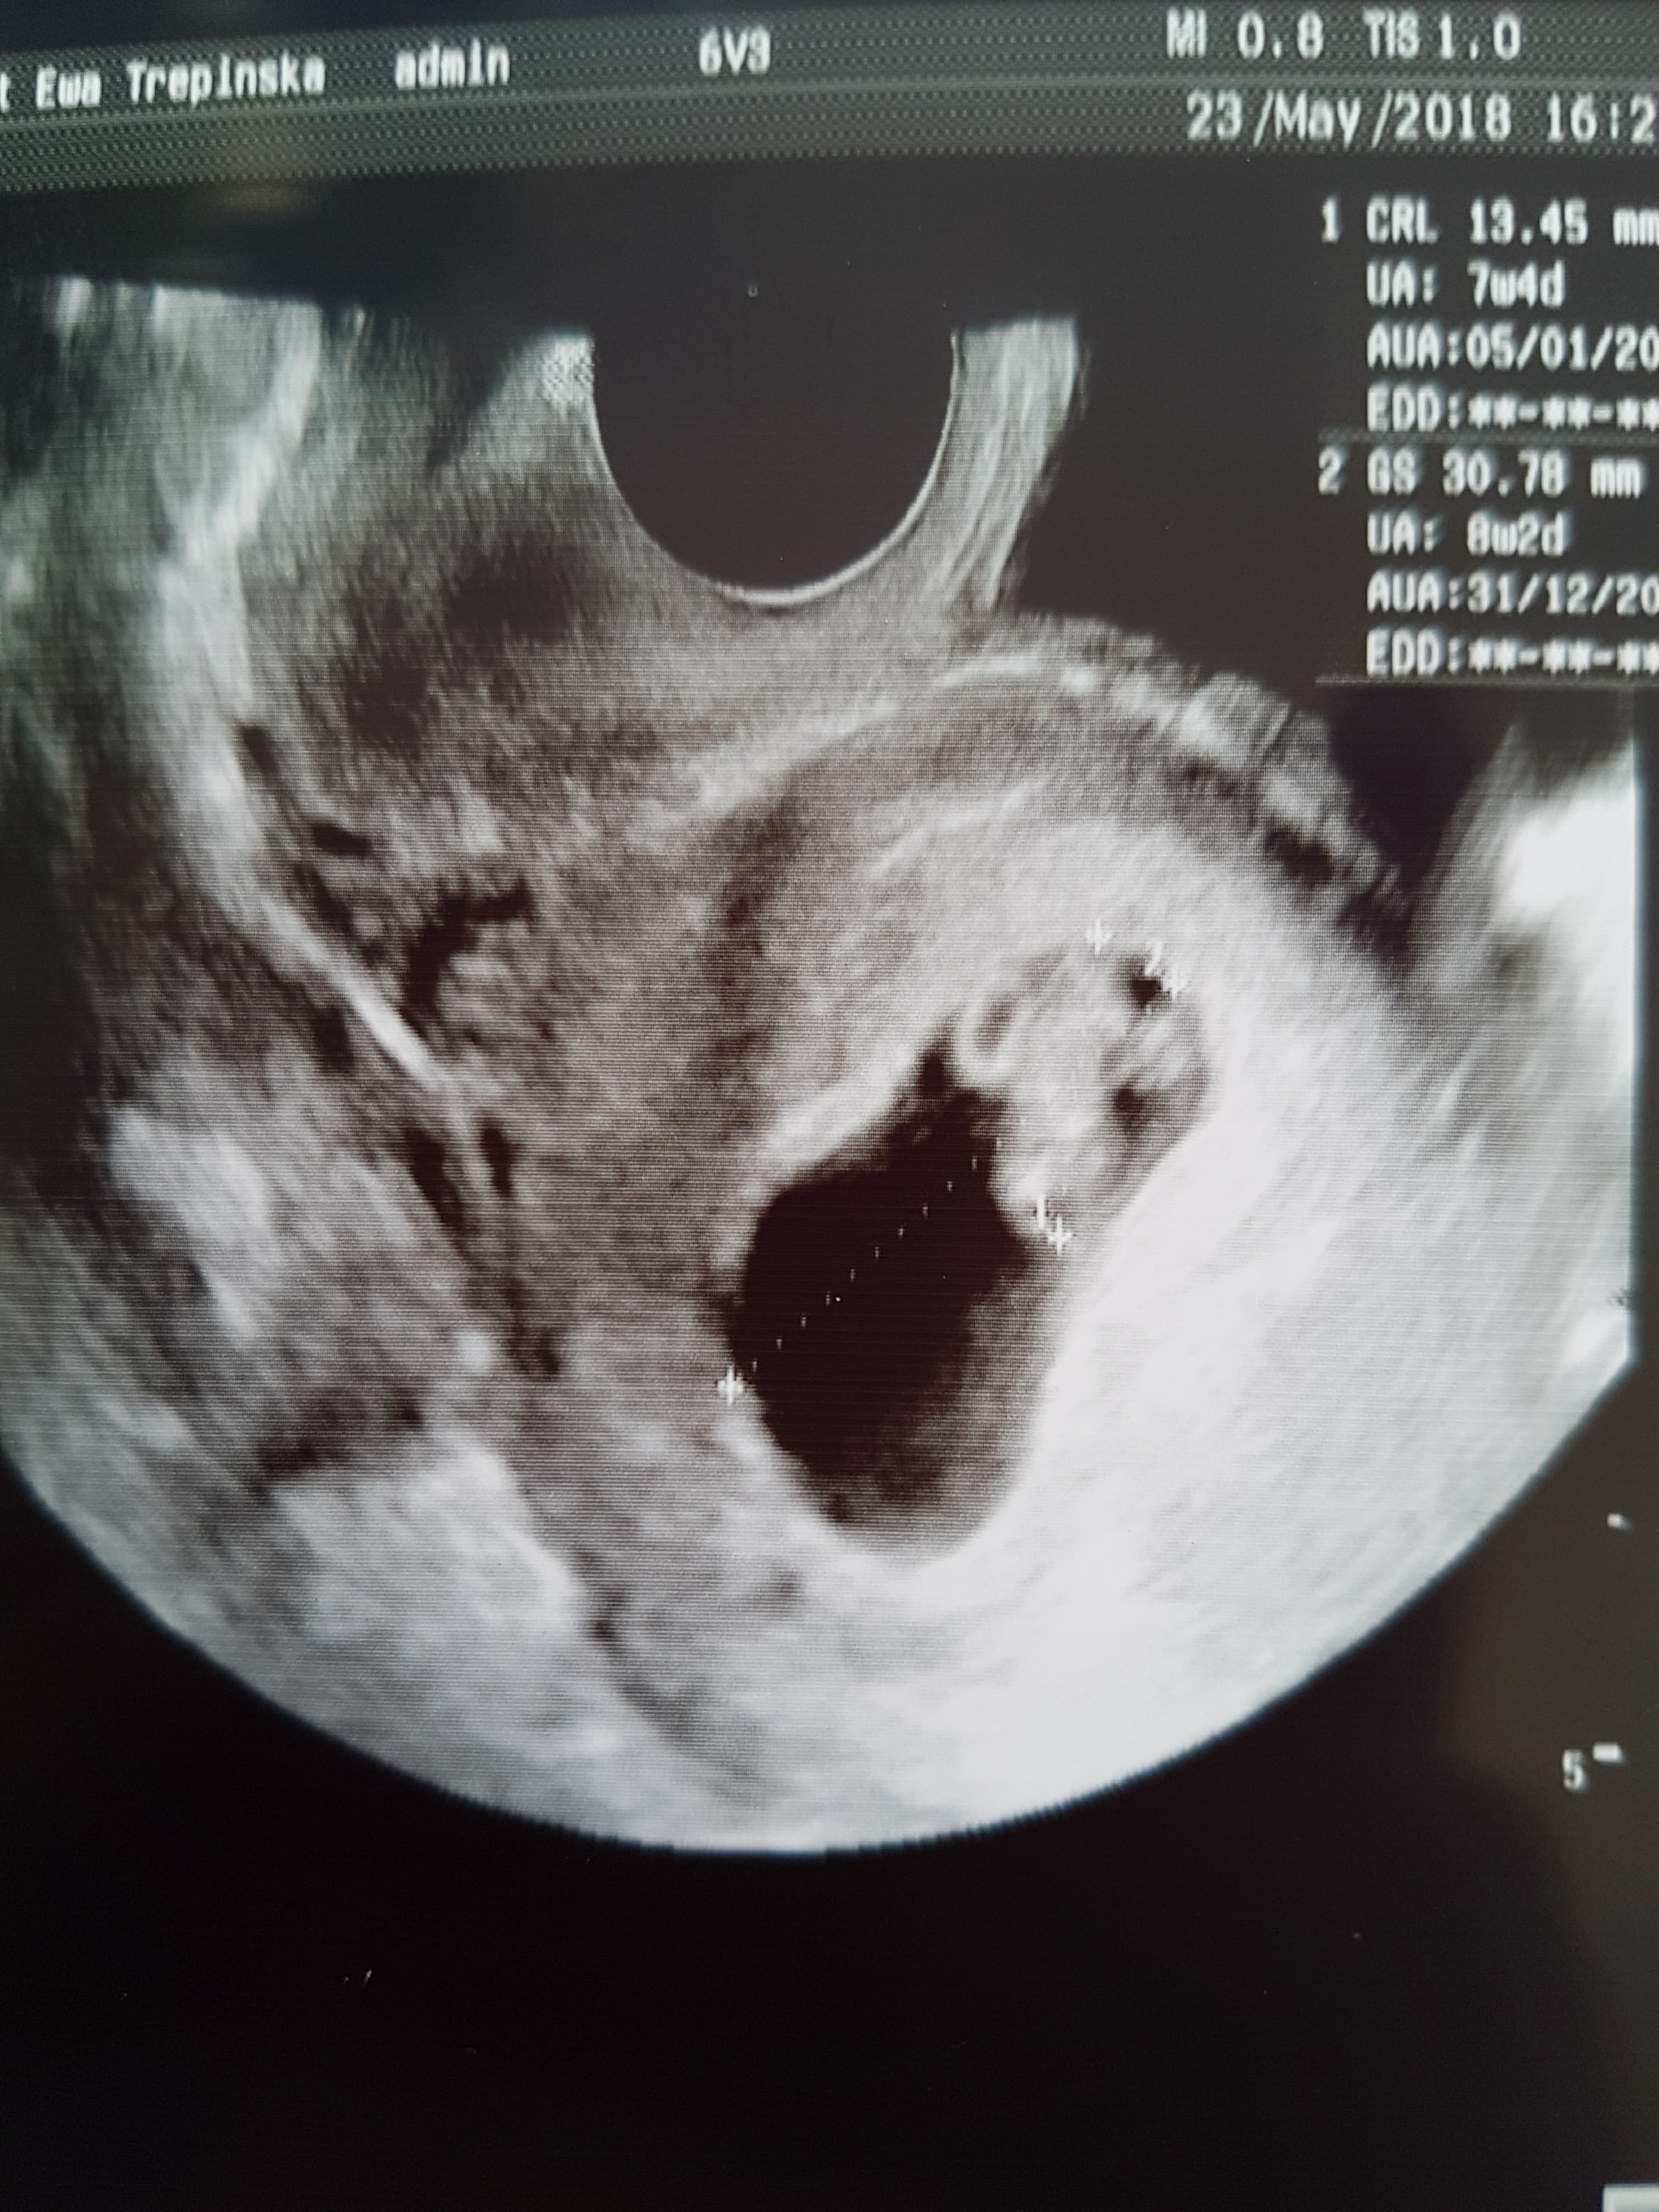

Superrr [emoji16] gratuluję pięknej kruszynki cieszę się bardzo i pozdrawiam